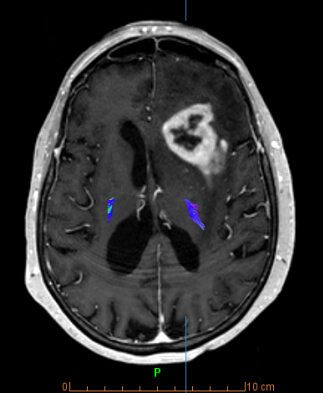

Οι ειδικές τεχνικές μαγνητικής τομογραφίας παίζουν σημαντικό ρόλο στην ανίχνευση και στην αξιολόγηση της έκτασης του καρκίνου, καθώς και στη διερεύνηση πολλών παθήσεων του Κεντρικού Νευρικού Συστήματος. Με την χρήση τους, η διαγνωστική ακρίβεια κατά την ταυτοποίηση και τον χαρακτηρισμό μιας βλάβης αυξάνεται σημαντικά, συμβάλλοντας έτσι στην επιλογή της κατάλληλης θεραπείας και τη σωστή παρακολούθηση του θεραπευτικού αποτελέσματος.

- Με πολλαπλές εφαρμογές στην ογκολογία (στη διάγνωση, τον προεγχειρητικό και ακτινοθεραπευτικό σχεδιασμό, στην παρακολούθηση του θεραπευτικού αποτελέσματος) και σε πολλές άλλες παθήσεις του εγκεφάλου, της σπονδυλικής στήλης και του τραχήλου (μεταβολικές, νευροεκφυλιστικές, φλεγμονώδεις και λοιμώδεις παθήσεις).

- Συνδυασμός των ειδικών τεχνικών με ανατομικές εικόνες υψηλής ευκρίνειας, ο οποίος δίνει σημαντικές επιπρόσθετες πληροφορίες για τον χαρακτηρισμό του ιστού (αριθμό των κυττάρων, αιματική ροή και μεταβολική δραστηριότητα)